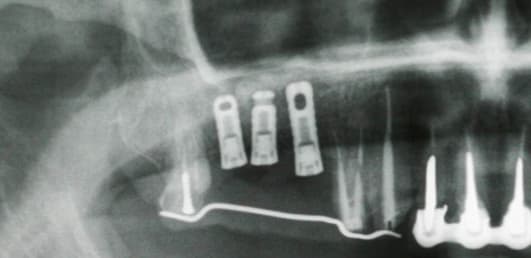

Bonjour à tous pouvez vous me dire le nom de ses implants

C'est bonnnnn j'ai trouvé ce sont des vieux implants BIOTECH